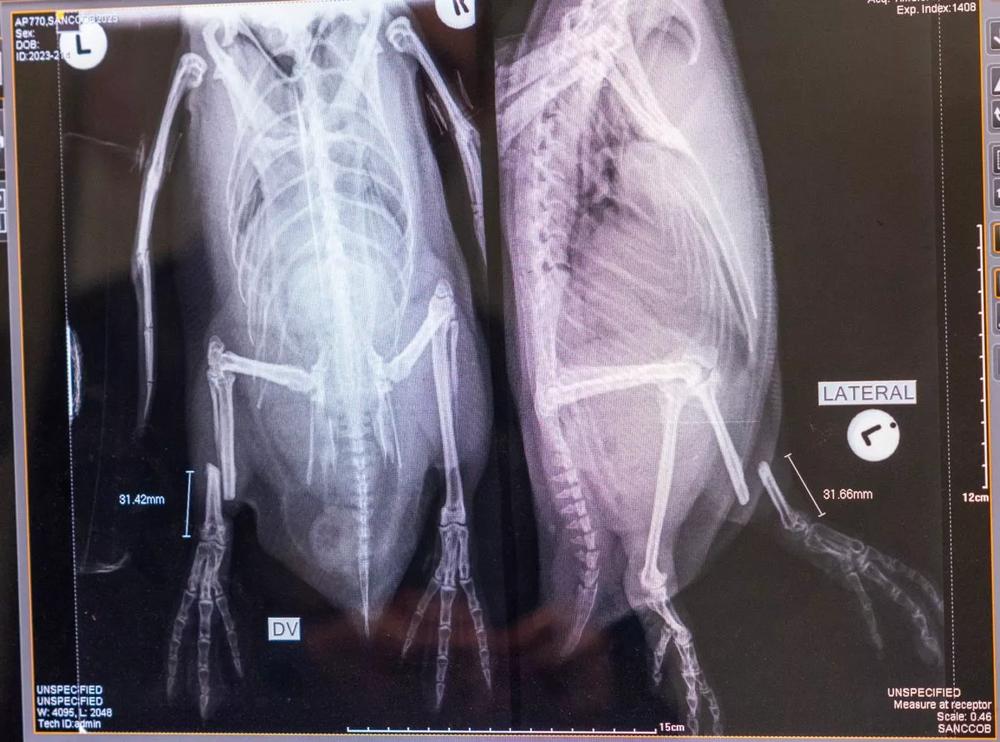

В этом году сотрудники южноафриканского центра позаботились о 279 африканских пингвинах. Основная задача центра спасения – спасти слабых птиц из дикой природы, восстановить их здоровье и выпустить обратно, чтобы они успешно продолжали род. Так специалисты стараются сохранить популяцию. Некоторые из пингвинов по прибытии в центр спасения ужасно истощены, у них замедлен сердечный ритм, а у многих встречаются проблемы с лёгкими. Одним пингвинам ставят капельницы и переливают кровь, если это необходимо, крошечных птенцов кормят сардинами каждые два часа, делают другие процедуры и всячески заботятся о них.

Помимо исчезающих пингвинов, среди пациентов центра – пингвины, подвергшиеся нападению собак, проглотившие леску или попавшие под колеса автомобилей. Еще одна серьёзная угроза для пингвинов – разливы нефти, которые тоже причиняют вред их здоровью.